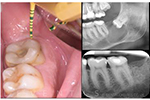

• Uzupełnianie brakującej kości podczas implantacji natychmiastowej.

• Zachowanie wyrostka zębodołowego.

• Regeneracja ubytków przyzębia.

• Podnoszenie dna zatoki szczękowej.